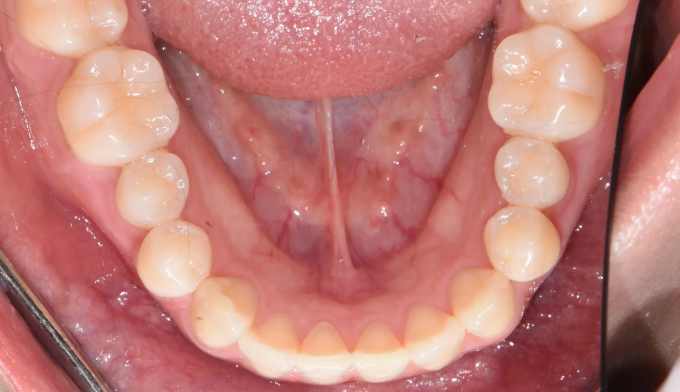

총 치료기간은 15개월 소요되었습니다.

거꾸로 물려있던 앞니를 앞으로 보내면서, 아래치열은 사랑니발치 후 미니스크류를 이용하여 후방이동시켰습니다.